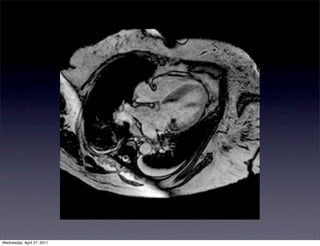

80 yo F with PMH of HTN, HLD, DM, CVA

with a history of continuous chest pain x 2

weeks. Patient was found to have a LBBB on

unknown duration. Cardiac enzymes were

negative. The patient was transferred to

WHC for further management.